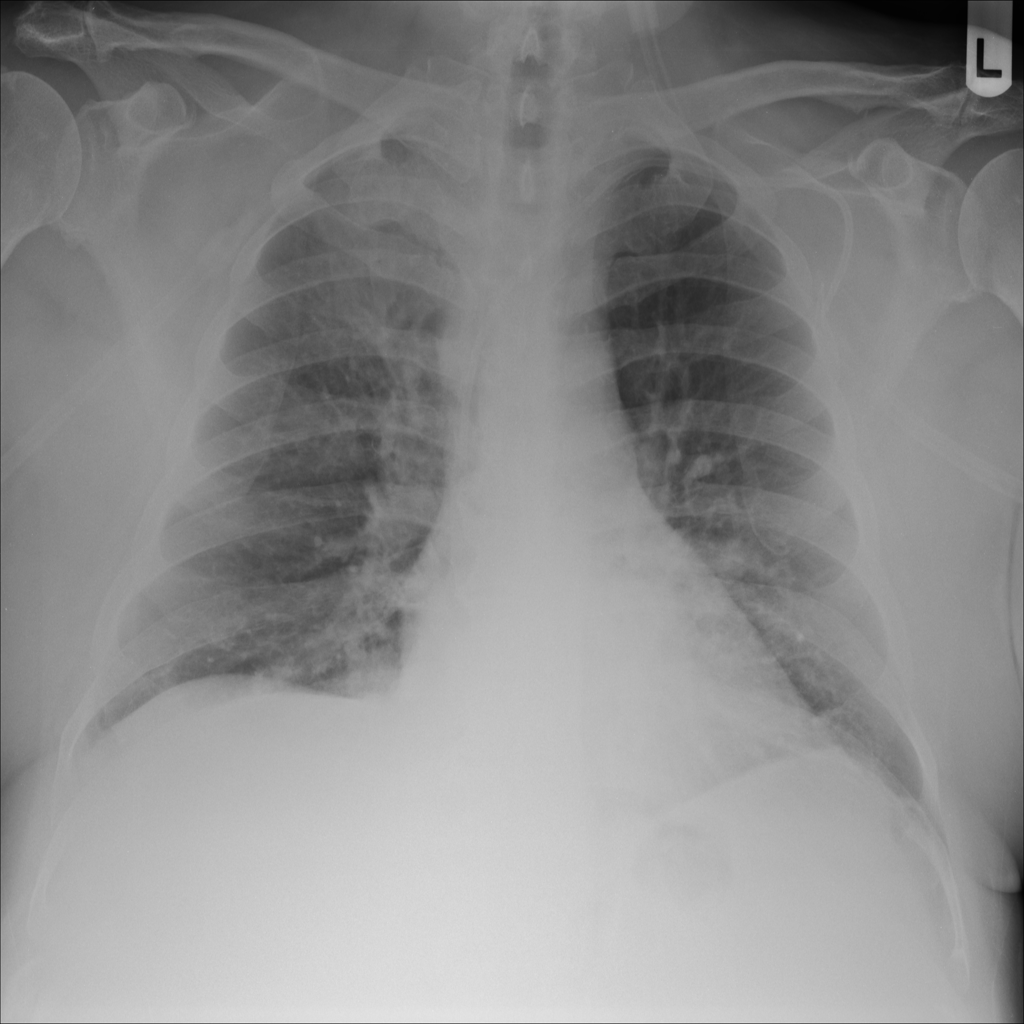

PAT-C1A7 · IMG-004Consolidation

PAT-C1A7 · IMG-004

PA